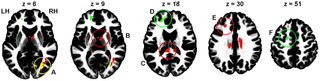

Regarding DTI data, between-group comparisons did not reveal any differences between questionnaire-based groups, whereas for performance-based groups, the High > Low risk-taking group contrast revealed significant FA differences. Similarly, only positive correlation between the total number of Go responses (i.e., risky decisions) and FA were found. Because both between-group and covariate analyses were based on the same measure (number of Go responses), their results expectedly demonstrated partial overlap (Fig. 1, Table 1). In particular, the right occipital WM area (Fig. 1, A) was highly significant in both analyses. Another area of overlapping results was located beneath the left prefrontal cortex (BA 9, 10, 46; Fig. 1, D), although with only a bordering significance (p = 0.051) for the between-group analysis. Other clusters were obtained only in one of the analyses. Thus, the High > Low risk-taking group difference was most prominent in the splenium of the corpus callosum (Fig. 1, C). The same contrast also revealed a left frontal subgyral WM difference next to BA 9 and 46 (Fig. 1, E) and a cluster in the anterior internal capsule next to the right thalamus (Fig. 1, B). Positive correlation between FA and number of Go responses were found in the anterior frontal region in the vicinity to BA 10 and 32, as well as under the premotor cortex (BA 6; Fig. 1, F).

Figure 1. Areas of significant (cluster size p<0.05 after FWE correction) difference between performance-based High and low risk-taking groups (red), areas of positive correlation between the total number of Go responses and FA (green), and overlap of these two results (yellow). The areas closest to cluster maxima are marked in the same colors as the contrast results that achieved significance (red or green) or both (yellow). The clusters are shown overlaid on the ICBM152 WM template, so that slices correspond to (or close to) z coordinate (from left to right: 6, 9, 18, 30, and 51 mm, MNI space) of maximal voxel values within significant clusters. The letters A, B, C, D, and F indicate the corresponding cluster peak location between the figure and Table 1. A: right occipital WM; B: right anterior internal capsule; C: splenium; D: left anterior frontal subgyral WM; E: left frontal subgyral WM; F: left premotor subgyral WM; LH: left hemisphere; RH; right hemisphere. https://doi.org/10.1371/journal.pone.0112780.g001